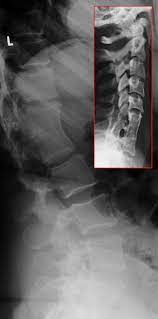

Lumbar Canal Stenosis

Narrowing of the spinal canal in the lower back, leading to back pain, leg heaviness, cramps, and difficulty walking long distances.

OLF

Thickened, hardened ligament at the back of the spinal canal compresses nerves, causing back pain, leg weakness and walking problems.

Osteoporotic Vertebral Fractures

Weak, brittle bones due to osteoporosis cause spine fractures with sudden back pain, height loss, stooped posture, and difficulty standing or walking.